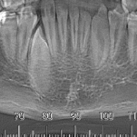

CONHEÇA NOSSA ROTINA CIRÚRGICA